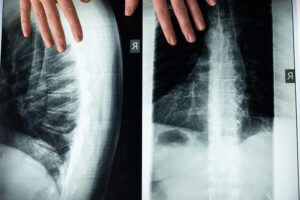

We specialize in the diagnosis and correction of the vertebral subluxation complex, removing neurological interference and restoring nerve impulse communication between nervous system and your body.

Back Pain Chiropractic

Spinal Decompression Treatment

Spinal Decompression

DTS Spinal Decompression Therapy, a traction based procedure, is one of the leading long-term treatment options